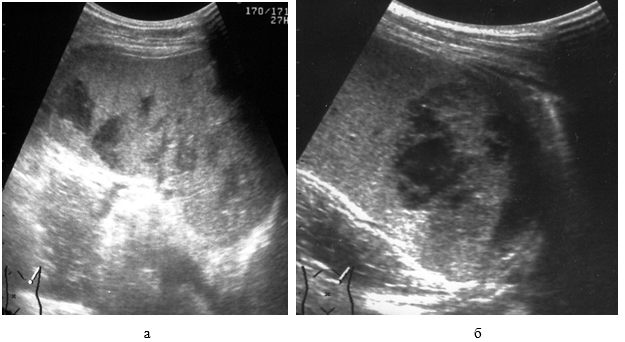

Эхографическая визуализация жидкости только в полости малого таза соответствует «малому» гемоперитонеуму, объем крови при этом не превышает 7,3 мл/кг массы тела (рис. 11).

Рис. 11. «Малый» гемоперитонеум: 1 – мочевой пузырь; 2 – кровь.

При «среднем» гемоперитонеуме, помимо малого таза, кровь эхографически определяется в печеночно-почечном кармане, латеральных каналах, периспленическом пространстве, ее объем колеблется от 7,6 до 25,8 мл/кг массы тела (рис. 12).

Рис. 12. «Средний» гемоперитонеум: 1 – печень; 2 – почка; 3 – кровь.

Нахождение жидкости еще и под передней брюшной стенкой в области мезогастрия соответствует «большому» гемоперитонеуму с объемом крови в брюшной полости более 26,7 мл/кг массы тела (рис. 13).

Рис. 13. «Большой» гемоперитонеум: 1 – петли тонкой кишки; 2 – кровь.